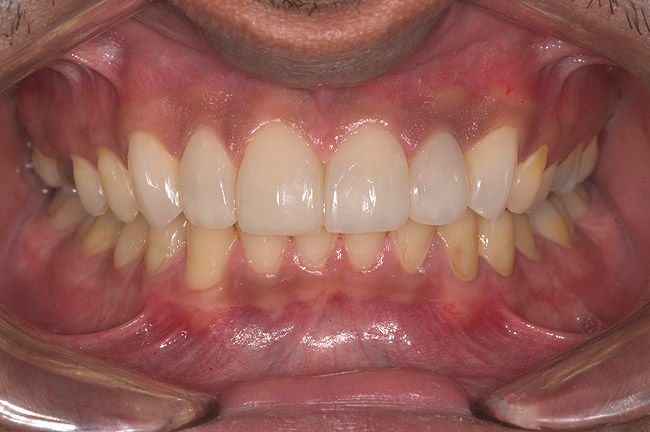

Figure 14  Postoperative smile.

Figure 14

Figure 15  Maximum intercuspation (MIP) after restoration of the lost palatal anatomy.

Figure 15

Figure 16  1:2 right lateral view; posteriors discluded in MIP.

Figure 16

Figure 17  1:2 left lateral view; posteriors discluded in MIP.

Figure 17

Figure 18  1:1 view of restored palatal surfaces with nanofilled resin.

Figure 18